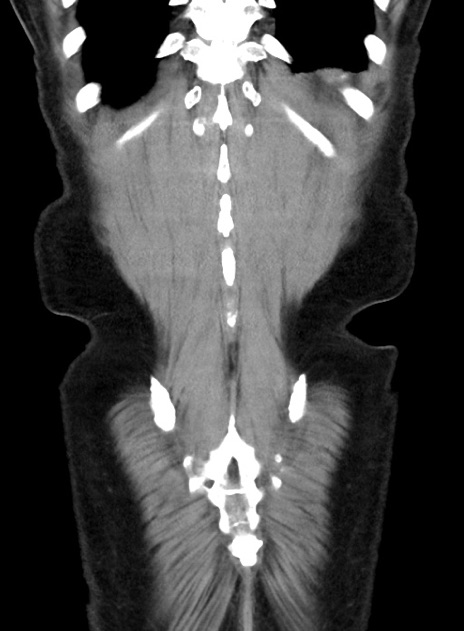

症例38(冠状断像)

【症例】70歳代 男性

【主訴】腹痛・嘔吐

【現病歴】昨晩より、嘔吐・腹痛あり。今朝になっても嘔吐あり。来院。

【既往歴】心臓バイパス手術、開腹胆摘、腸閉塞

【身体所見】BP 107/71mmHg、HR 116/min、腹部:平坦、軟、下腹部に軽度圧痛あり。反跳痛なし。

【データ】WBC 15100、CRP 0.32